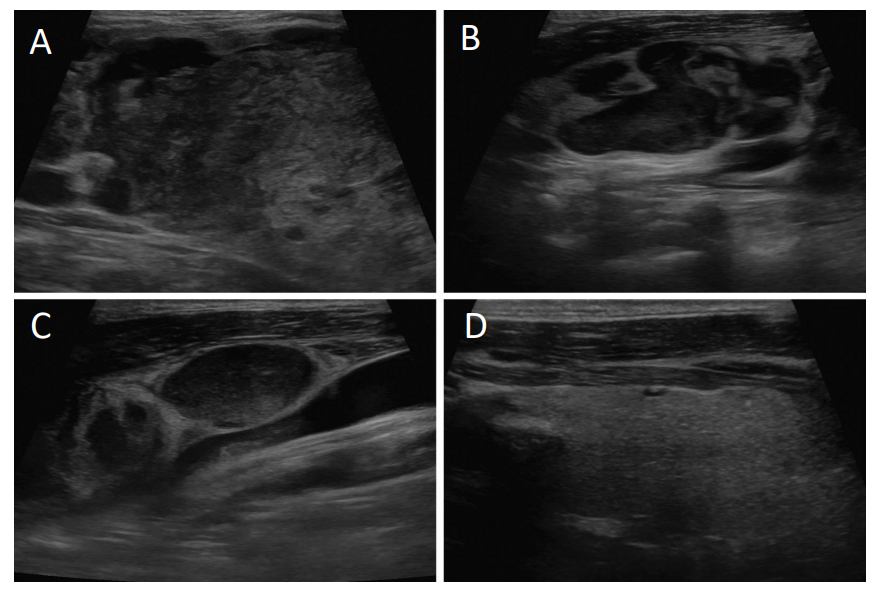

• 腹部CT显示肝脏肿块增大,淋巴结呈现弥漫性病变,并发现多处骨性病变。颈部超声检查发现右侧颈部淋巴结异常肿大,并有一个5.3 cm大小的异质性肿块占据右侧甲状腺的位置(图1),进行淋巴结活检,结果证实为转移性肝细胞癌(图2)。

图片

图1. 颈部超声。(A)甲状腺右叶伴有异质性肿块。(B)颈部右侧第3级淋巴结形态异常病变。(C)颈部右侧第3级和第4级淋巴结形态异常病变。(D)左侧甲状腺叶正常外观